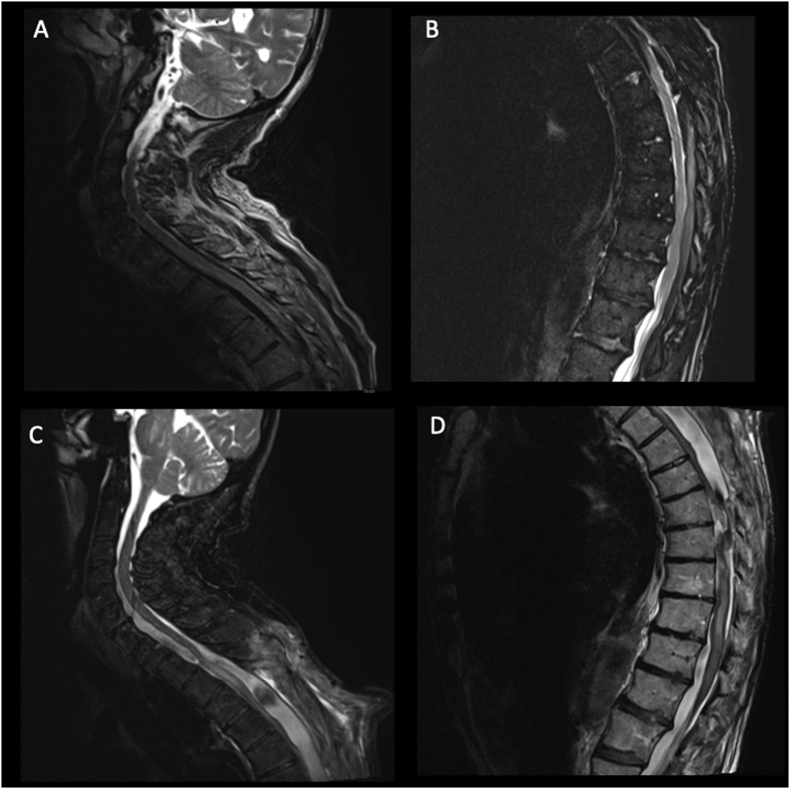

Figure 2.

Spinal sagittal T2-weighted MRI illustrating the preoperative status of our patient (A and B): an anterior and posterior subdural hematoma starting from the lower cervical spine (A) and going down to T12 (B) was detected and responsible for a flaccid paraparesis. The patient was operated for the evacuation of this symptomatic hematoma and a dorsal laminectomy wad performed for the microsurgical evacuation of the collection. In the postoperative period the patient presented a progressive neurological deterioration with a follow-up MRI showing the development of a large posterior SAC, with an important mass effect on the spinal cord (C, cervical and D, dorsal).